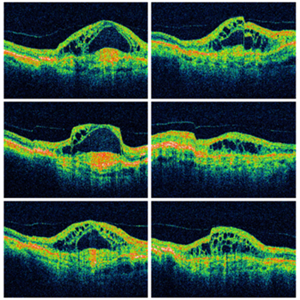

OCT of a Posterior Vitreous Detachment

OCT of a posterior vitreous detachment.

Condition/keywords: optical coherence tomography (OCT), posterior vitreous detachment